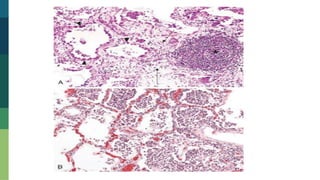

Granuloma Pulmonar

Necrosis caseosa

Imagen de una necrosis caseosa, rodeada de linfocitos

Necrosis caseosa Imagen deuna necrosis caseosa, rodeada de linfocitos